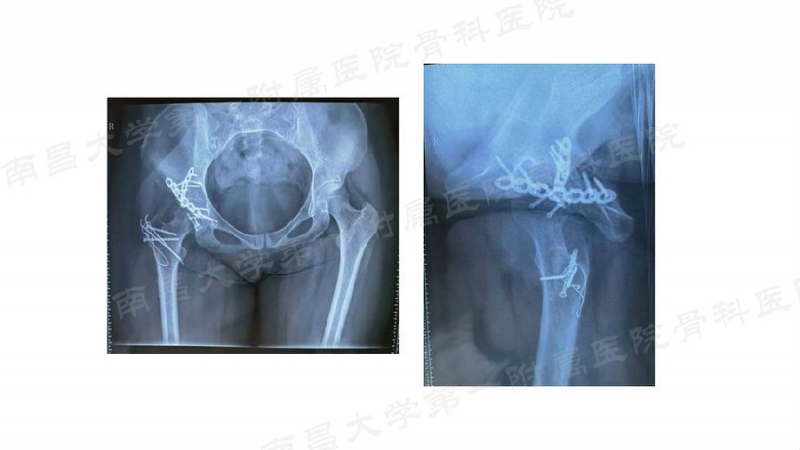

病例分享

病例一

病例二

病例三

病例四

病例五